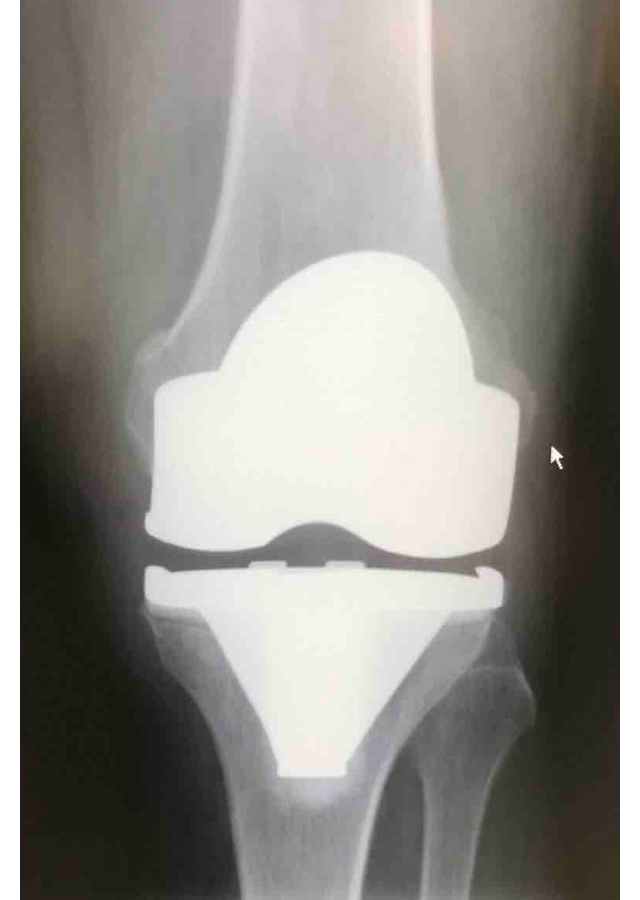

Csípő és térd ízületi betegségek protetizálása

Degeneratívtól, posttraumáson át veleszületett deformitásokig, revíziók, egyszerű és bonyolult helyzetek megoldása.